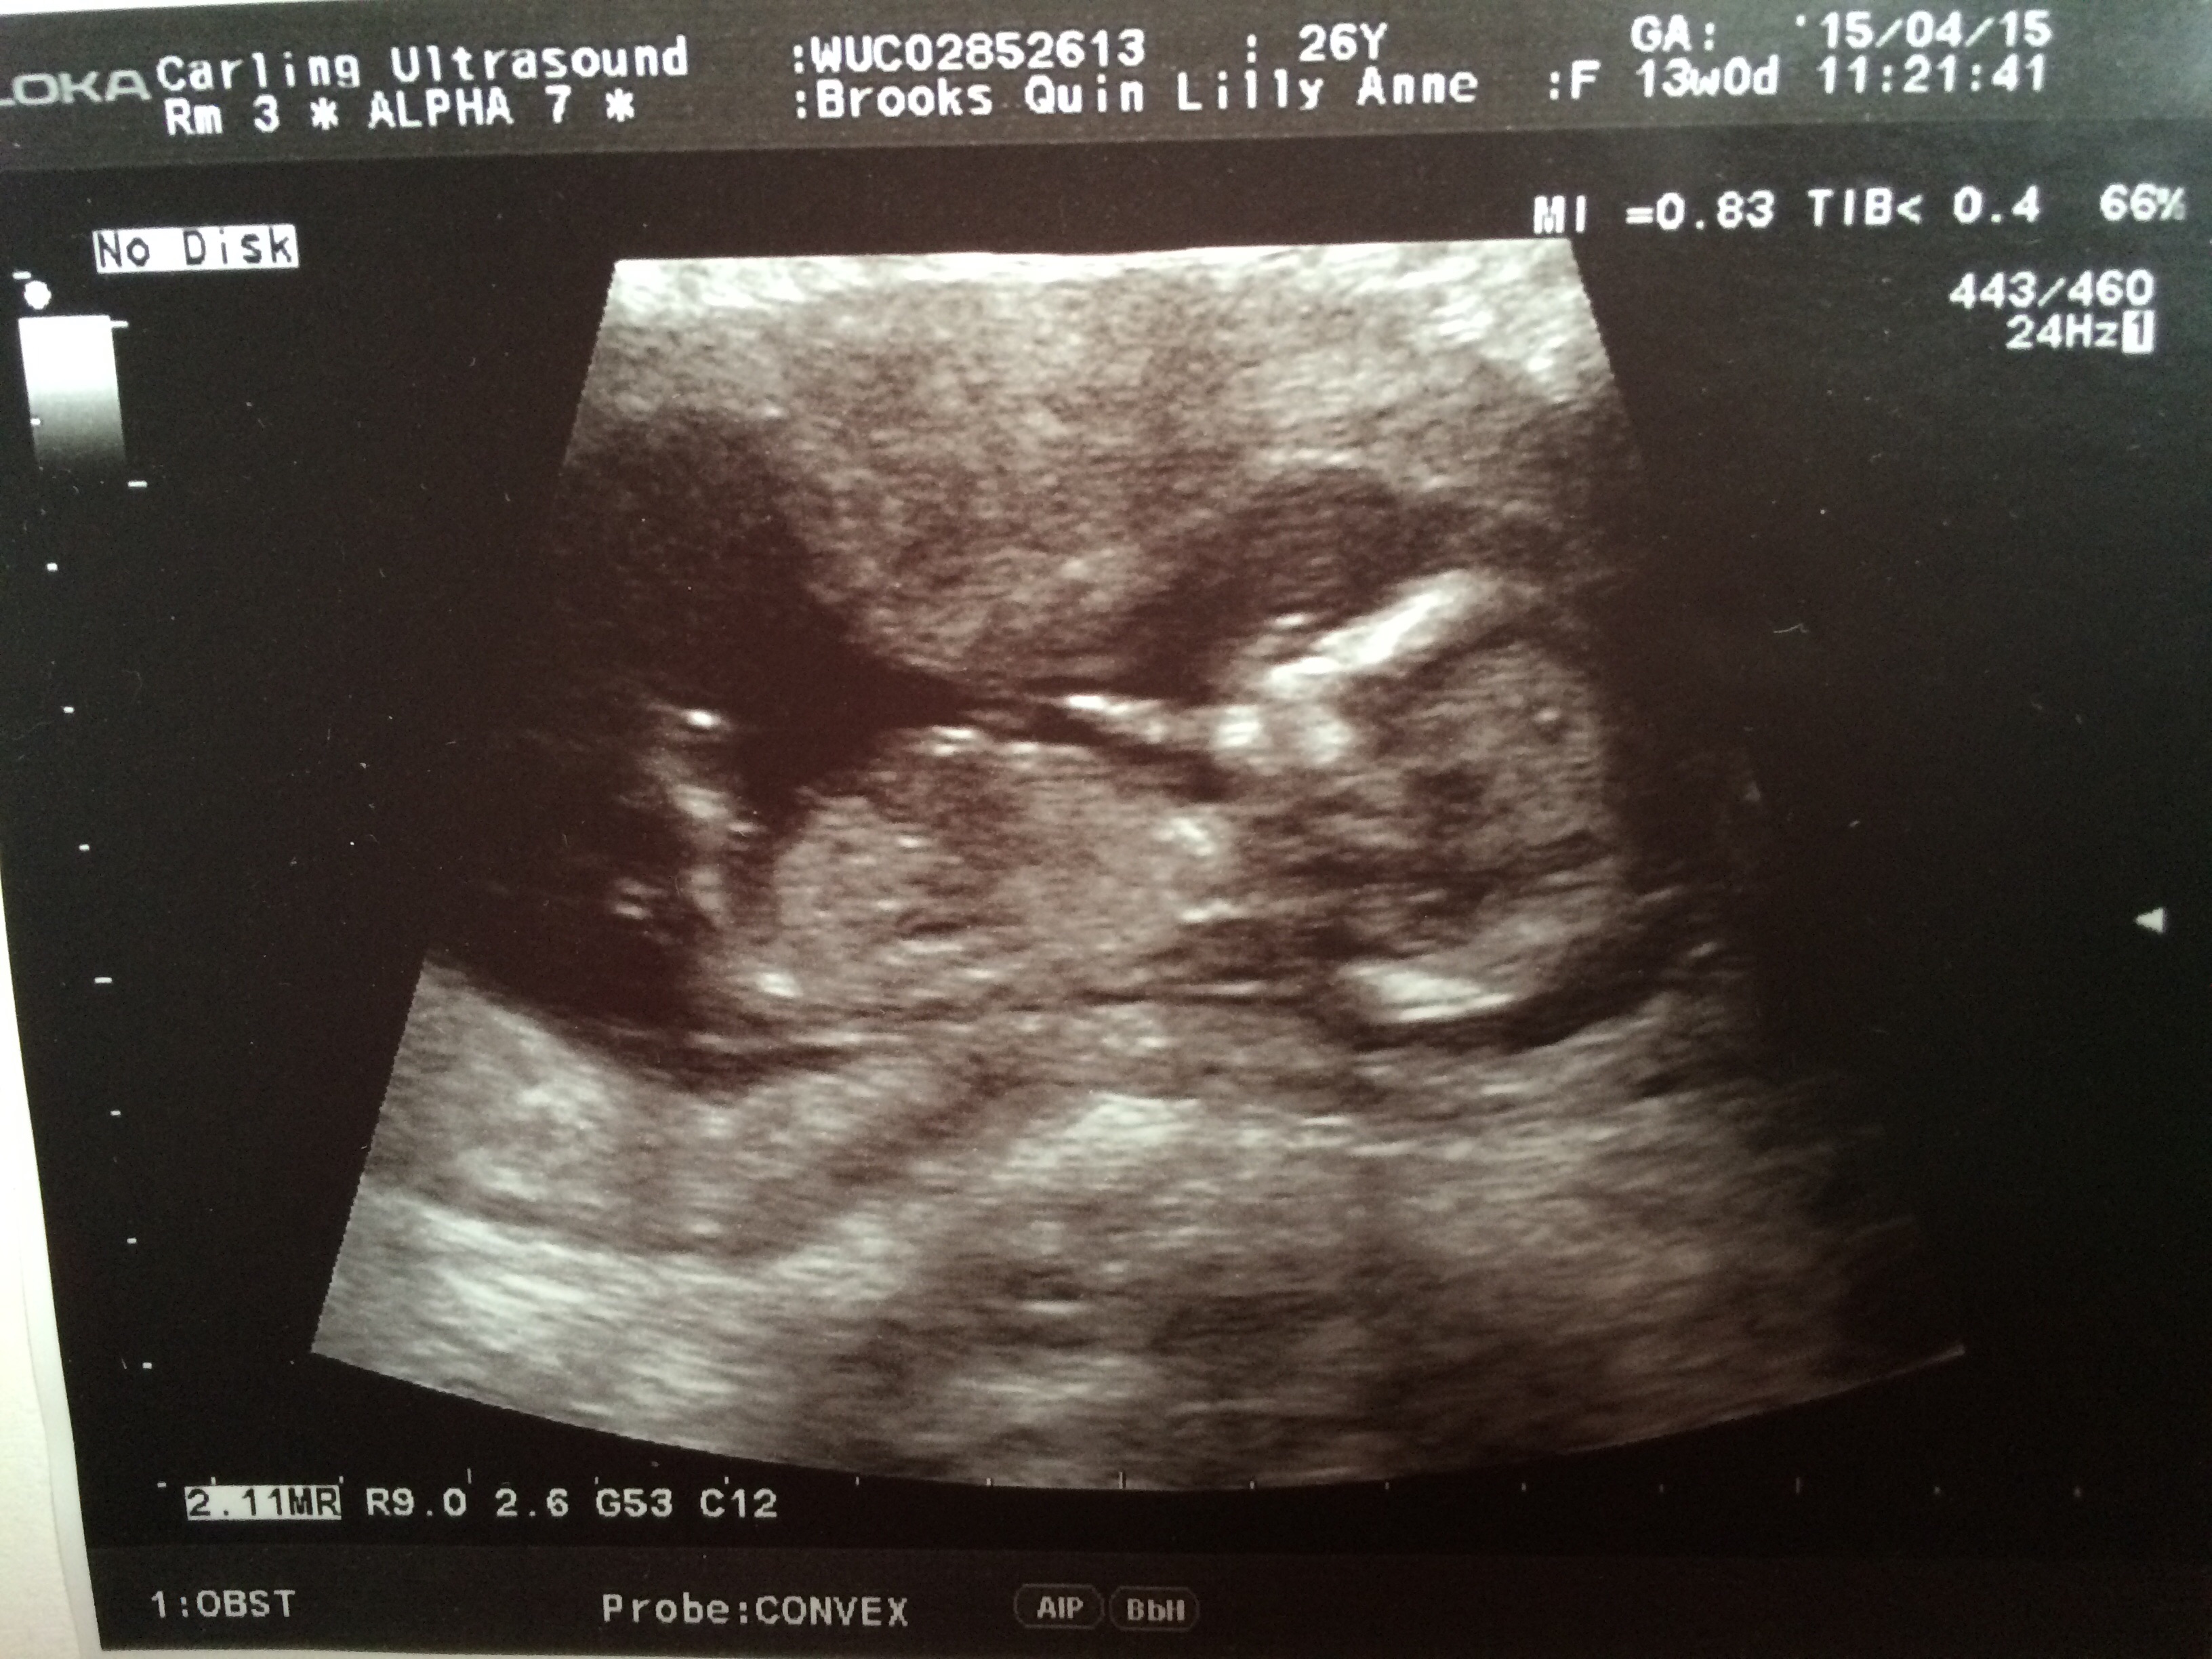

Possibly boy from the top scan

boy lean

I am leaning girl based on the first pic. I was able to zoom in and saw a forked, flat nub.

Leaning girl based on first pic.

ooh thats right on the line between boy and girl angle.

Hard to see but I'm giving a girl lean. GL :)